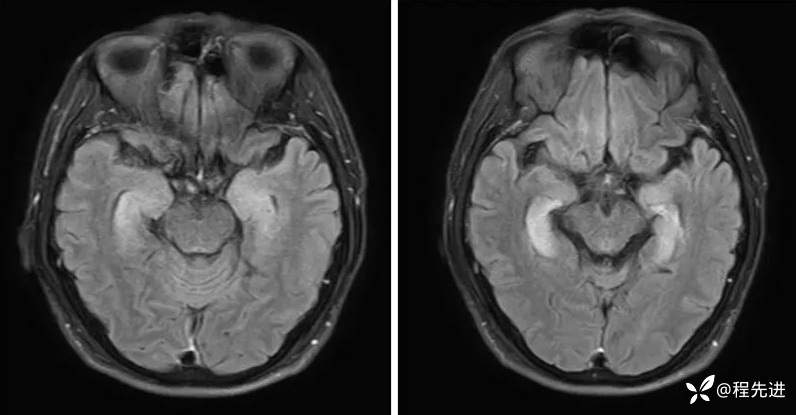

MRI平扫+增强:

FLAIR:

DWI、ADC: